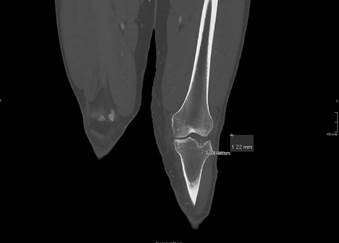

Hombre de 24 años, obeso, derivado de urgencias de AP por dolor, deformidad e impotencia funcional de la rodilla izquierda tras caída en bicicleta. No presenta heridas externas. En urgencias, tras asegurar la presencia de pulso distal y sensibilidad, procedemos a una valoración radiológica (figura 1), donde apreciamos una luxación anterior femorotibial. Bajo sedoanalgesia, reducimos la luxación y revaloramos la integridad neurovascular. Exploramos la integridad ligamentosa apreciando inestabilidad multidireccional: cajón posterior +++ y valgo +++. Inmovilizamos a 30º con férula posterior, comprobamos radiológicamente la reducción, sin apreciar fracturas, y derivamos al paciente a nuestro hospital de referencia, donde una angiotomografía computarizada (angio-TC) descarta lesiones vasculares, pero detecta una fractura de hundimiento de la cara anterior de la meseta tibial externa (figura 2), confirmada posteriormente con una resonancia magnética (RM), que además determina las lesiones musculoesqueléticas asociadas a la luxación: rotura de ligamento cruzado anterior (LCA), rotura parcial del ligamento cruzado posterior (LCP), rotura del ligamento colateral medial (LCM), rotura del tendón semimembranoso y tendones de la pata de ganso, y rotura del menisco interno. Se inmoviliza con fijador externo (figura 3) y se interviene 18 días más tarde, iniciando la rehabilitación al día siguiente, inicialmente con movilización suave, carga progresiva desde el primer mes, bicicleta sin resistencia a partir del segundo mes y piscina. Como secuela, 6 meses después de la lesión, presenta un leve bostezo en valgo que no le impide caminar. Dos años más tarde, hace vida normal, incluyendo laboral y deportiva.